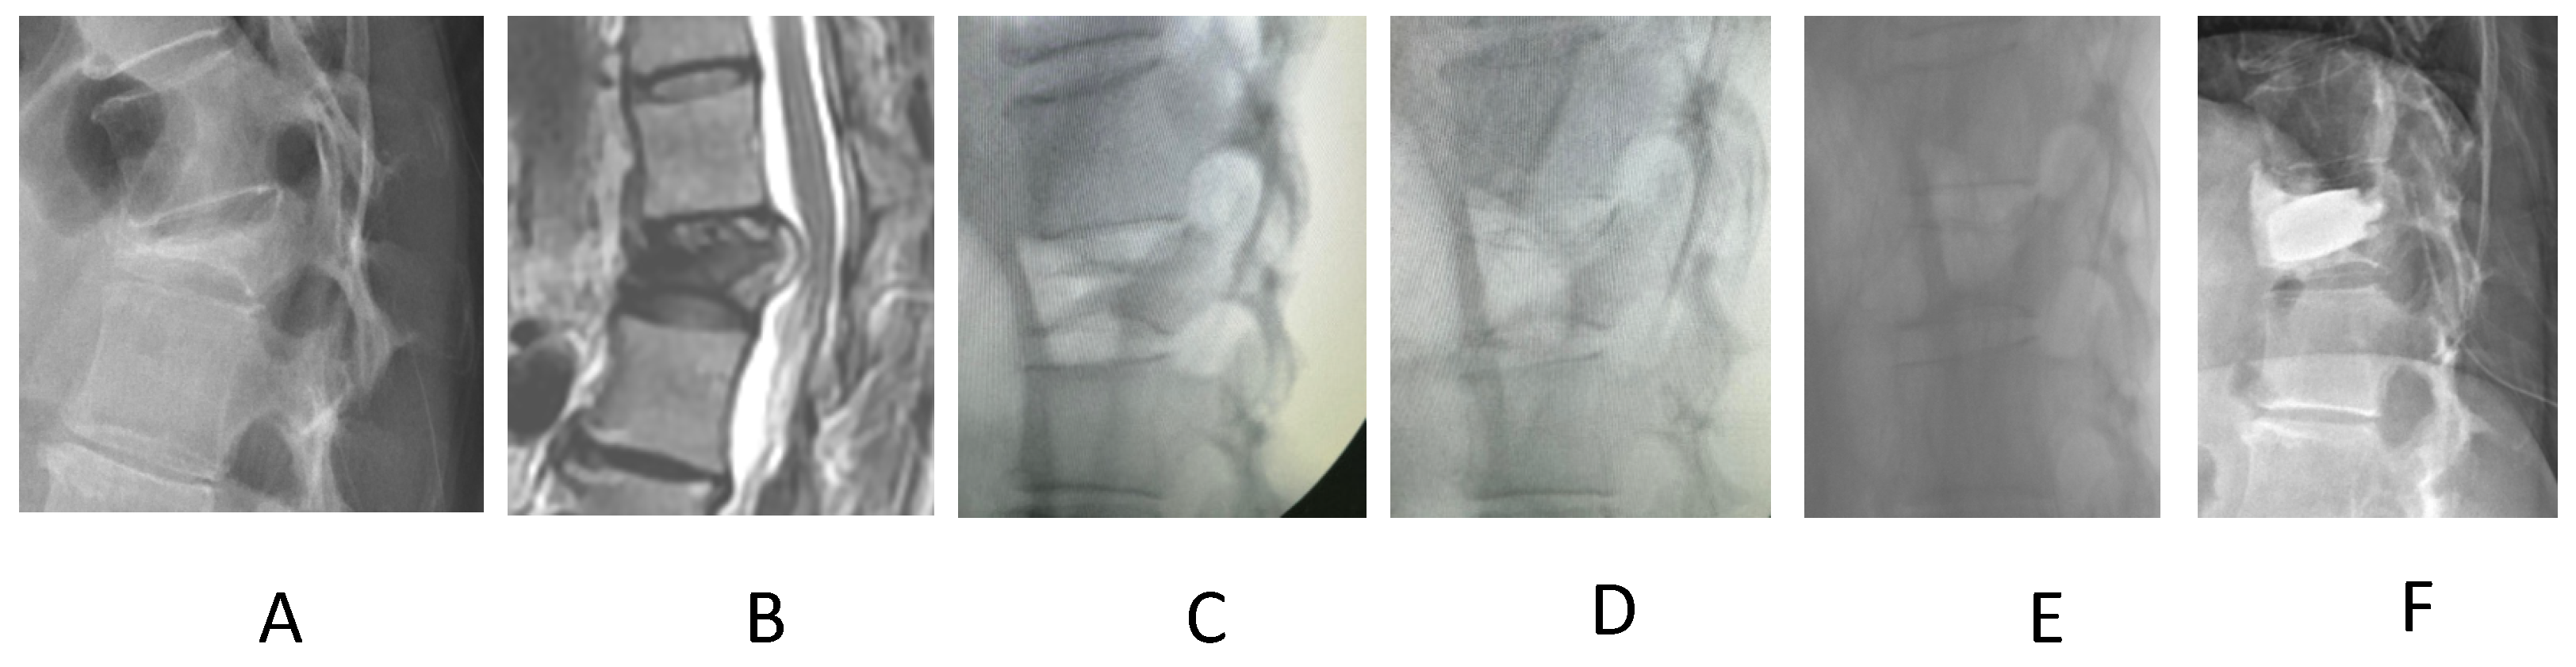

Manual Reduction for Subacute Osteoporotic Burst and Severe Compression Thoracolumbar Fractures

2. Materials and Methods

3. Results